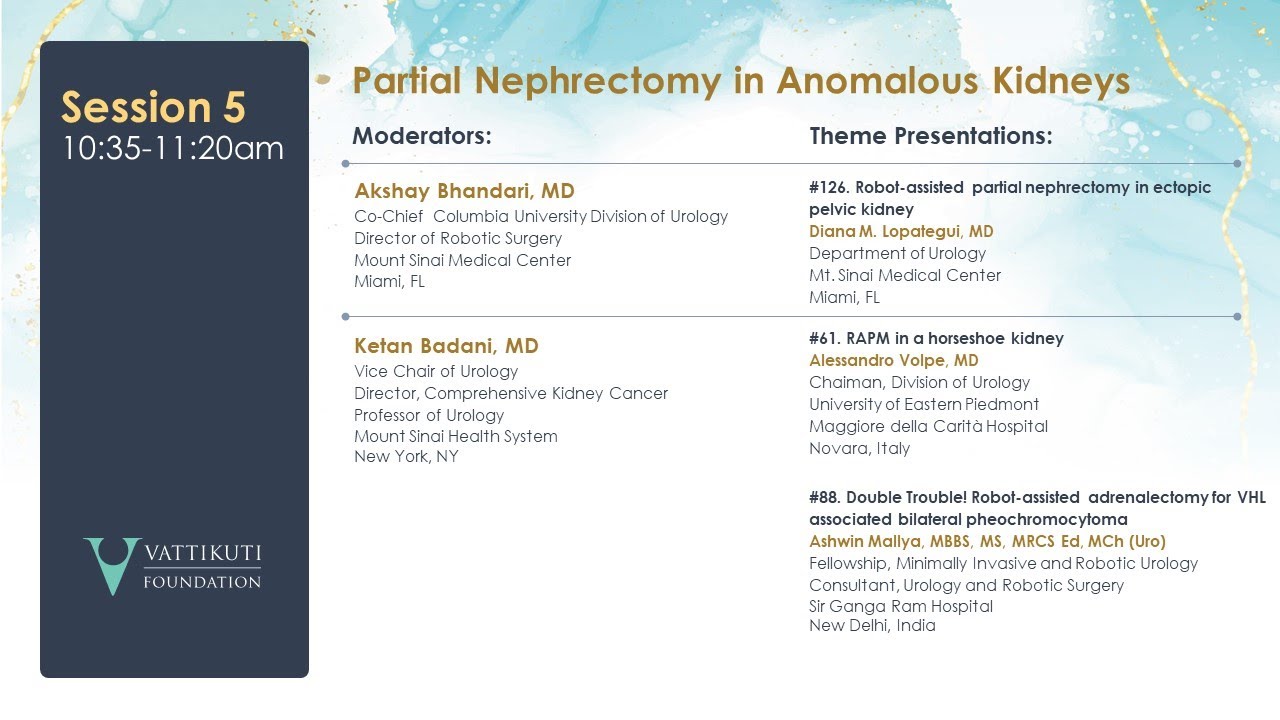

Robot Assisted Partial Nephrectomy in Ectopic Pelvic Kidney

Robot Assisted Partial Nephrectomy in a Horseshoe Kidney

Humans of Robotic Surgery, KS Awards, Robotics, Surgeon, Video Library ';